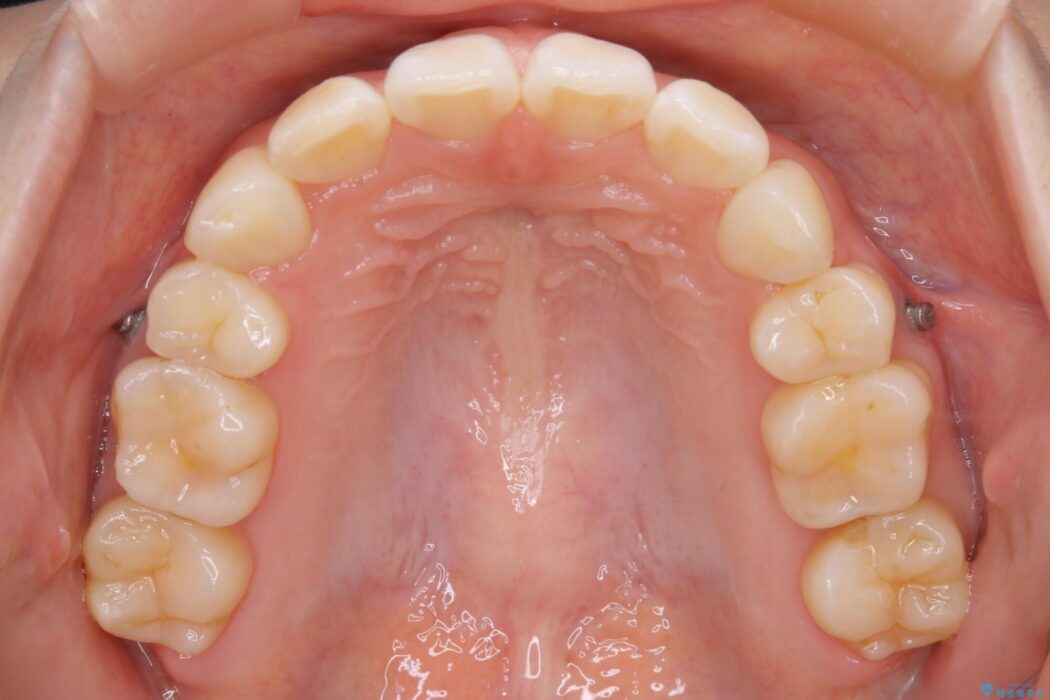

治療後について

後戻りしていた歯列もきれいに整い患者様にはご満足いただけました。

小学生~高校生の間に矯正治療をされている方で、その後の成長や生活の変化におけるリテーナー(後戻り防止装置)の継続使用が困難となり、叢生(ガタつき)が時間の経過で再発してしまうケースが多くあります。

一度目の矯正治療の際に抜歯をしていたり後戻りでのガタつきの度合いによって再矯正における治療期間が最初の矯正治療と同程度に要する場合もあります。